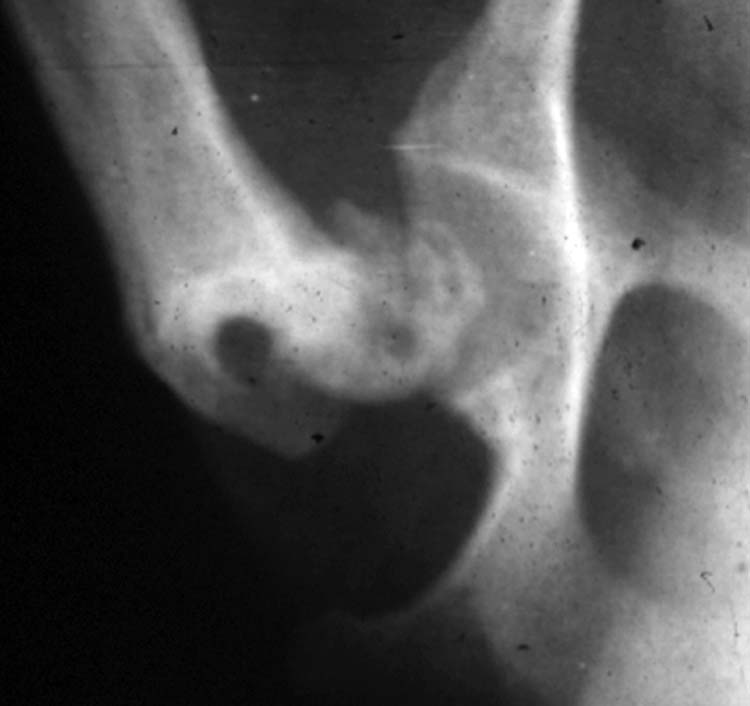

Legge-Perthes disease (ischaemic necrosis of the femoral head)

This condition typically affects smaller breeds of dog (e.g. West Highland White Terrier) and occurs during development. The head of the femur loses its blood supply and the bone collapses leading to a misshapen femoral head and secondary osteoarthritis. Cases with chronic pain can be treated surgically (THR or excision arthroplasty).